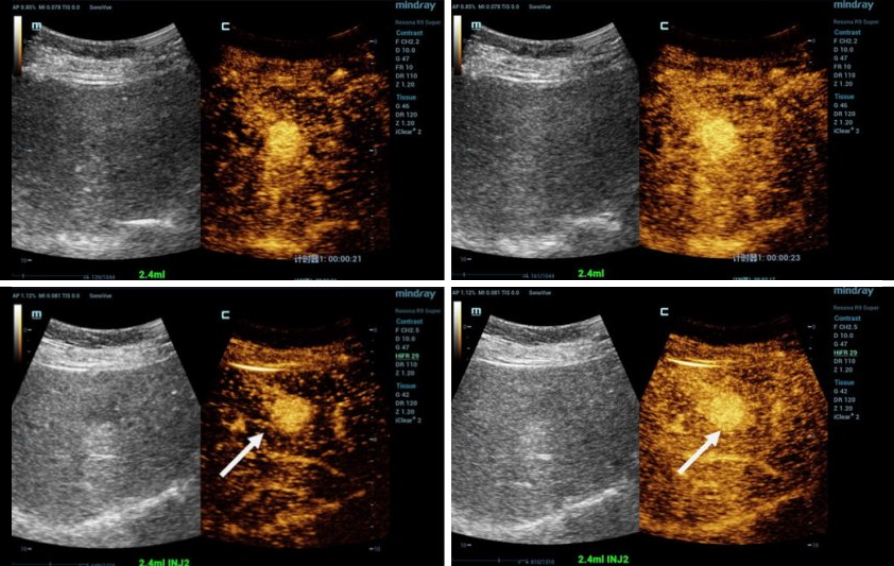

?? 6? ?? ??? ??? ????? HiFR CEUS(????? ?? ?? ???)? ??? ??? ???? ??? ????? ?? ?? ? ??? ? ???? ??? ? ???? ?????.

Yi Dong: '?? ??? ???? ??? ???? ?? 3cm ??? ?? ? ??? ?? ???? ???? ????. ?? ????? HiFR CEUS? ??? ??? ??? ?? ??? ???? ????? ??? ??????. HiFR CEUS? ??? ??? ???, ? ?? ?? ? ??? ??? ??? ??? ??? ?????. ?? ?? ??? ??? ??? ? ??? ?? ???? ?? ????. HCC(??? ??)? ?? ?? ????? ?? ??? ???? ????? ?? ??? ? ??? ?????? ?? ??? ??? ??? ??????.'

Yi Dong: 'HiFR CEUS? ?? ???, ??? ? ???? ???? ?? ? ?? ???? ?? CEUS? ??? ??? ?????. ???? ??? ? ?? ?? ??? ?? ?????. ??? ??? HiFR CEUS? ??? CEUS?? ????? ?? ???? ?? ??? ? ?? ???, ? ? ?? ??? ??? ????? ???.'

Yi Dong: '??? ??? ????? ??? ?? ?? ??? ??? ??? ?? ? 10??????. ??? ???? HiFR CEUS ???? Mindray Resona 9? ?? ? ????. ?? ?? 100?? ??? ??? ? ????. ??? ?? ????? ?? ??? ? ? ????? ?? ?? ?? ?? ??? ??? ??? ? ? ?????. ??? ???, CEUS? ?? ???? ??????. ???? ??? ?? CEUS ??, ?? ?? ?? ??, ?? ?? ??, ?? ? ?? ?? ?? ?? ??? ??? ?? ????.'